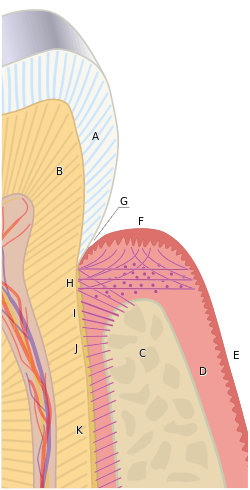

The most coronal position of untouched tooth structure (that is, the continual line of original, undrilled tooth structure at or near the gum line) is referred to as the margin. This margin will be the future continual line of tooth-to-restoration contact, and should be a smooth, well-defined delineation so that the restoration, no matter how it is fabricated, can be properly adapted and not allow for any openings visible to the naked eye, however slight. An acceptable distance from tooth margin to restoration margin is anywhere from 40-100 μm. However, the R.V. Tucker method of gold inlay and onlay restoration produces tooth-to-restoration adaptation of potentially only 2 μm, confirmed by scanning electron microscopy; this is less than the diameter of a single bacterium.

Naturally, the tooth-to-restoration margin is an unsightly thing to have exposed on the surface of a tooth visible in a smile. In such a circumstance, the dentist would like to place the margin as far apical (towards the root tip of the tooth) as possible, even below the gum line. While there is no issue, per se, with placing the margin at the gumline, problems may arise when placing the margin too subgingivally (below the gumline). First, there might be issues in terms of capturing the margin in an impression to make the stone model of the prepared tooth (see stone model replication of tooth in photographs, above). Secondly, there is the seriously important issue of biologic width. Biologic width is the mandatory distance to be left between the height of the alveolar bone and the margin of the restoration, and if this distance is violated because the margin is placed too subgingivally, serious repercussions may follow. In situations where the margin cannot be placed apically enough to provide for proper retention of the prosthetic crown on the prepared tooth structure, the tooth or teeth involved should undergo a crown lengthening procedure.